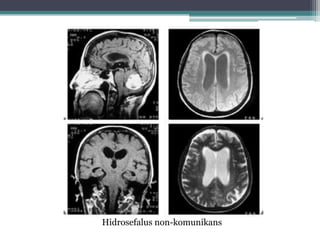

MRI

dilatasi ventrikel

penyebab dari hidrosefalus

penipisan dari korpus kalosum

Hidrosefalus non-komunikans